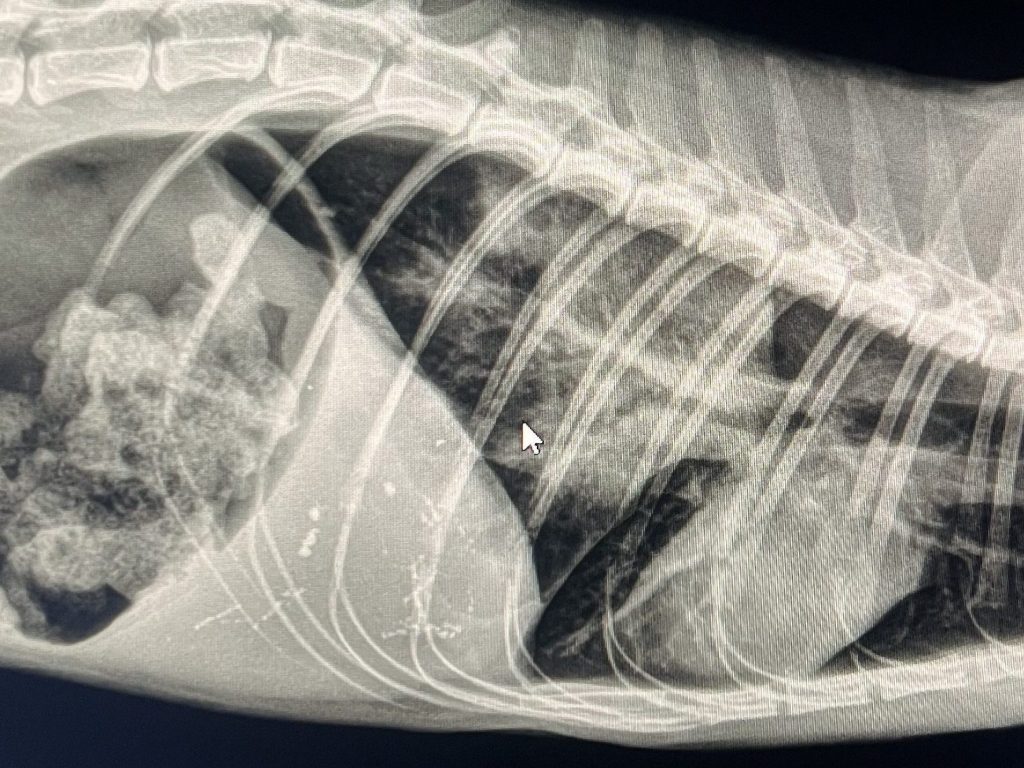

RTG jamy brzusznej

Wykorzystywane w diagnostyce niedrożności przewodu pokarmowego, obecności ciał obcych, rozszerzenia lub skrętu żołądka.